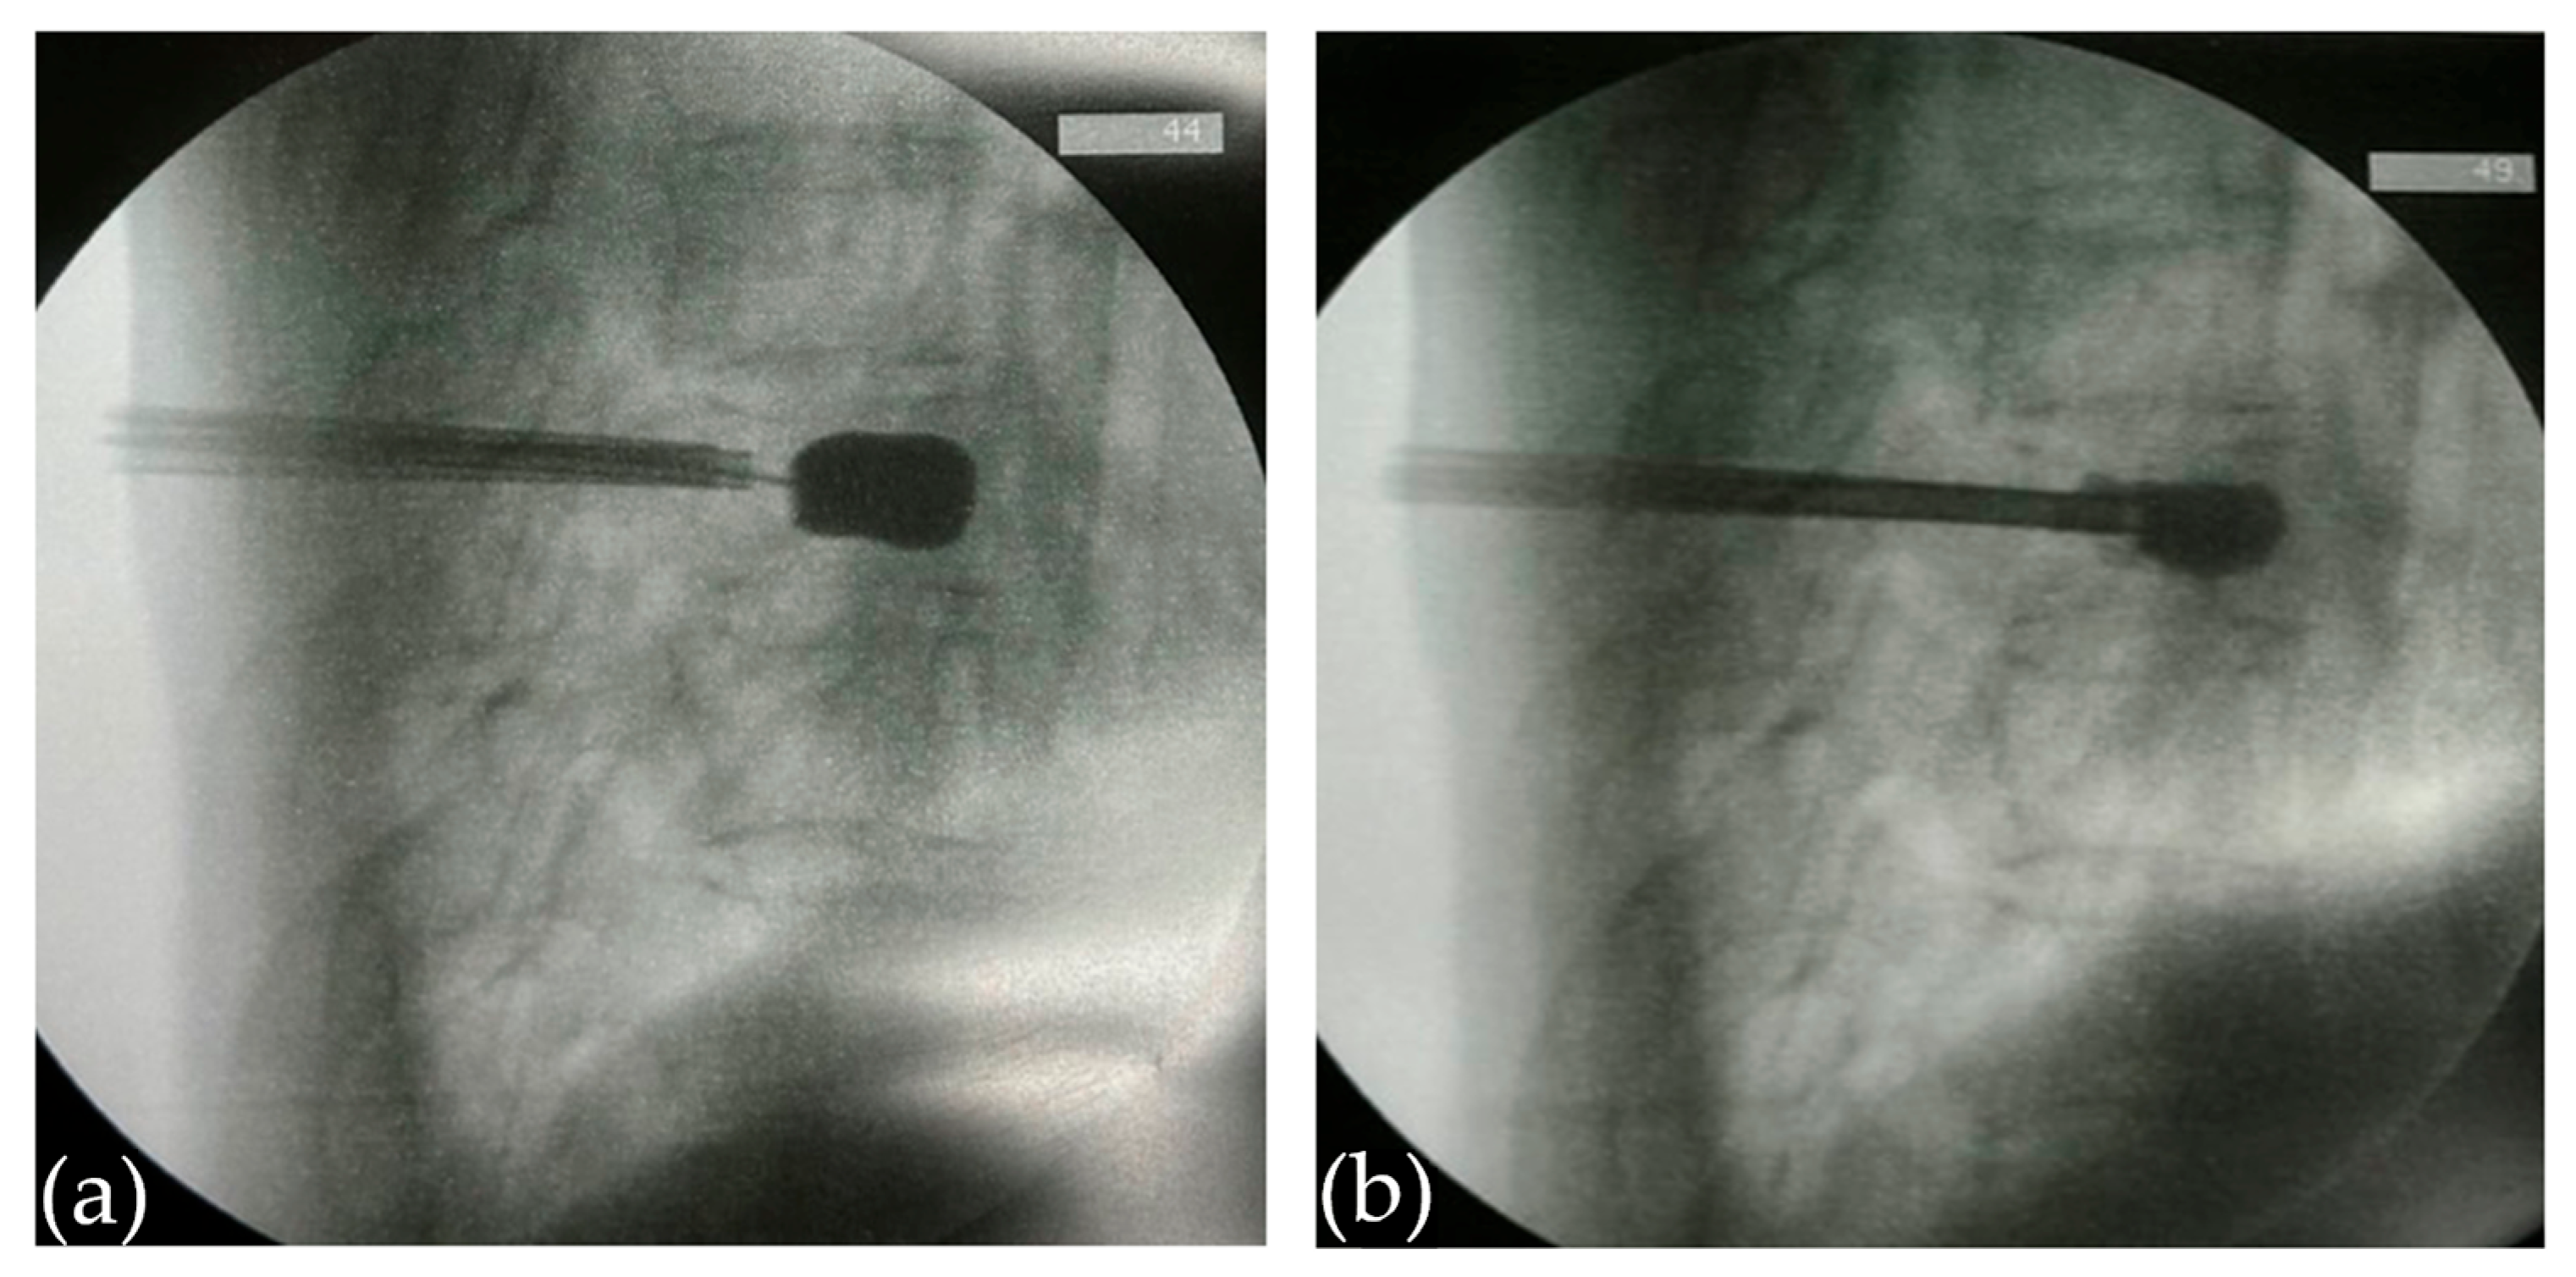

2.2.1. Creation of a Vertebral Cavity

2.2.2. Cement Preparation and Initial Injection

3.1. Surveillance of Cement Leakage

3.2. Decompression Maneuver